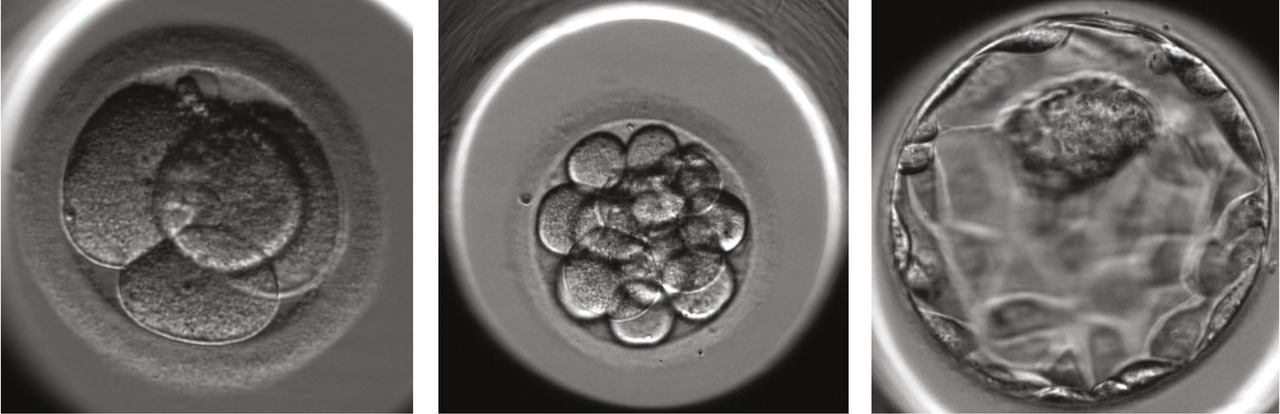

Selon les régions, entre 14 et 45 % des tentatives de fécondation in vitro en France (fécondation in vitro classique ou avec injection intracytoplasmique d’un spermatozoïde) aboutissent à l’obtention d’un nombre d’embryons supérieur à celui qu’il est possible (ou souhaitable) de transférer in utero sans prendre le risque de grossesses multiples de haut rang. Ces embryons dits « surnuméraires » sont donc congelés et conservés dans les centres d’assistance médicale à la procréation (AMP) pour les couples afin de les utiliser lors d’une tentative d’AMP ultérieure. De plus, l’arrivée de la vitrification embryonnaire a considérablement augmenté le bénéfice de la congélation embryonnaire qui est passé de 8 % de naissances additionnelles en 1998 à 18 % en 2015.1 Ainsi, selon les données du registre de l’Agence de la biomédecine, plus de 68 000 embryons surnuméraires ont été congelés au cours de l’année 2015 et 221 538 embryons étaient conservés dans les centres français d’AMP au 31 décembre 2015.1

– l’obtention de lignées de cellules souches pluripotentes à partir du bouton embryonnaire ; c’est la plus fréquente. Les lignées de cellules souches embryonnaires humaines ont un double intérêt, elles sont « immortelles » et « pluripotentes ». Elles peuvent être amplifiées au laboratoire, être congelées et décongelées, tout en gardant la potentialité de se différencier dans tous les tissus du corps humain. Cela les distingue d’autres cellules souches, comme les cellules souches hématopoïétiques de la moelle osseuse ou du sang de cordon, qui ne permettent d’obtenir que les cellules spécialisées de quelques tissus, voire d’un seul. Il n’est pas exclu qu’un jour se développent des « banques » de cellules différenciées à partir de cellules souches embryonnaires humaines qui pourraient être utilisées dans des protocoles cliniques à visée thérapeutique ;

– une meilleure connaissance de l’embryon lui-même, de son développement, de l’analyse des gènes ou des protéines exprimés dans les cellules de l’embryon, de ses interactions avec l’environnement. Cinq projets concernant ce type de recherche ont été autorisés par l’Agence de la biomédecine. Les techniques d’AMP ne permettent pas de remédier à toutes les formes d’infertilité. La meilleure connaissance des premiers stades du développement de l’embryon humain est une étape essentielle pour comprendre les causes des échecs de reproduction et améliorer la prise en charge des couples.